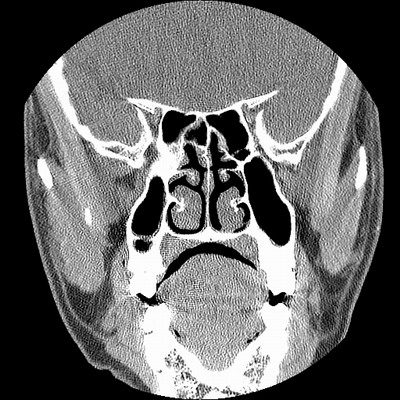

男,38岁,鼻塞、头痛2个月,要求鼻窦ct检查。

右侧上颌窦、蝶窦、筛窦、额窦及左侧上颌窦慢性炎症。

右侧鼻中隔左偏,右侧上颌窦、筛窦、额窦慢性炎性病变。右侧上颌窦开口粘膜增厚。

1)副鼻窦炎。2)右侧中鼻道及总鼻道粘膜息肉样变。3)双侧中下鼻甲肥大。4)鼻中隔轻度左突偏曲。